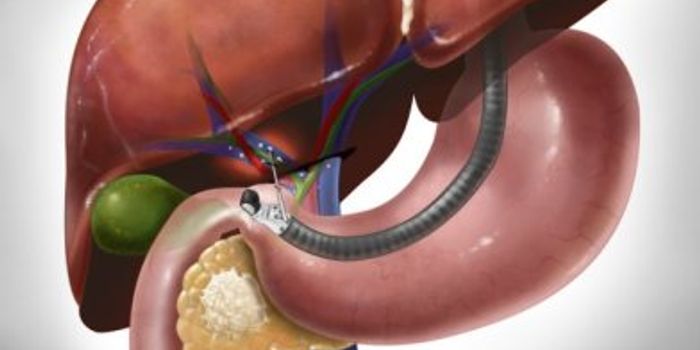

FEB 11, 2016Clinical & Molecular DXTo stop an aggressive, lethal killer known as pancreatic cancer, scientists have devised a way to deliver a toxic chemo ...

AUG 28, 2015CancerPancreatic cancer, the fourth deadliest cancer in the U.S., is very hard to detect in its early stages. Rarely diagnosed ...

NOV 30, 2015Clinical & Molecular DXPancreatic cancer has one of the worst mortality rates of all cancer types, largely because the cancer spreads rapidly a ...

AUG 02, 2017CancerTurmeric, the trendy spicy that’s making its way into lattes, could be key in defeating pancreatic cancer drug res ...

DEC 02, 2021CancerPancreatic ductal adenocarcinoma (PDAC) is the most common form of pancreatic cancer, accounting for about 90% of pancre ...

MAR 30, 2016Clinical & Molecular DXTo help treat pancreatic cancer, scientists are taking a step back to diagnose the disease before it becomes lethal. In ...

APR 12, 2017ImmunologyPancreatic ductal adenocarcinoma (PDA) usually kills those diagnosed within five years, due to the ability of pancreatic ...

JAN 13, 2022CancerThe American Cancer Society estimates the lifetime risk of pancreatic cancer at about 1 in 64. Pancreatic duct ...